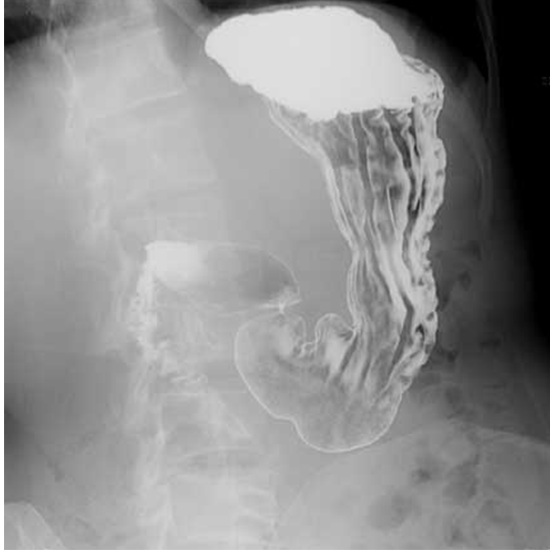

The Barium Meal Upper Gastrointestinal test examines the duodenum or small intestine. This test detects polyps, ulcers, and tumors in the small intestine or stomach.